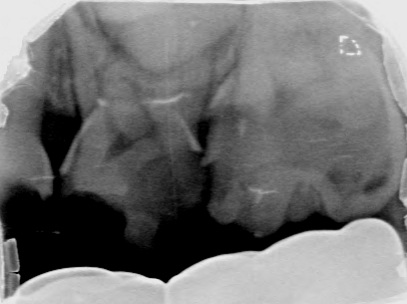

Afbeelding 3a: Röntgenfoto's op de leeftijd van 6 jaar, juli 2018.

Afbeelding 3b: Röntgenfoto's op de leeftijd van 6 jaar, juli 2018.

Afbeelding 3c: Röntgenfoto's op de leeftijd van 6 jaar, juli 2018.

Afbeelding 3d: Röntgenfoto's op de leeftijd van 6 jaar, juli 2018.

Jenny is 6 jaar. Er worden röntgenopnames en kleurenfoto’s gemaakt (Afb. 3 en 4). Op de röntgenfoto’s lijken de bovenmolaren ernstig aangetast, maar ze zijn hard en inactief. De niet-gerestaureerde bovenmolaren en kronen met gerestaureerde ondermolaren zijn vrij van ontsteking. Jenny kwam voor mondonderzoek om de 4-6 mnd.

Voor het maken van röntgenfoto’s werd een doormidden geknipt maat 0 fosforplaatje gebruikt. Maat 0 is voor veel jonge kinderen te groot en moeilijk te accepteren.